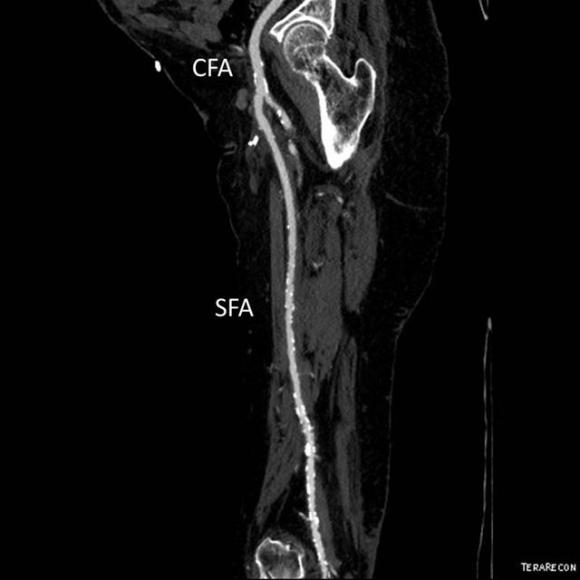

The patient is a gentleman from out of state who had called about problems he was having with walking and with leg ulcers that wouldn’t heal. He is in his seventies and has a pacemaker for an arrhythmia for which he was on Xarelto. He also had type II diabetes. He had bilateral lower extremity deep venous thromboses 6 years prior requiring IVC filter placement. The filter occluded, and it resulted in sudden sharp and debilitating pain in both legs with walking short distances -some days only 50 paces.He described it as an unbearable pain in calves and thighs that felt like his legs were going to burst. He also had ulcers on his legs that would heal with ministration but soon recur. This was all despite being quite active, with regular workouts, and being fit. He was compliant with compression. He sent a CT scan done last year (below).

It showed an Optease retrievable vena cava filter that was occluded and the iliac systems bilaterally (right above and left below) were chronically occluded with patent vena cava above and femoral confluences bilaterally below.

He had no hypercoagulability nor ongoing recent DVT’s. I thought there was a good chance that we would be able to recanalize the occluded iliocaval segment and he flew in for a consultation, and he was pencilled into the schedule ahead of his visit.

Examination revealed a fit and trim man in his 70’s in no apparent distress. He had bilateral leg edema that was moderate with small superficial and tender ulcers of the right posterior distal calf. Pulses were normal. He was taken to our hybrid suite and venography from femoral vein access in the proximal thigh in the supine position revealed his right and left iliac venous systems to be occluded (below figures).